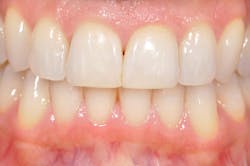

Figure 6: Immediate-load temporaries are finished.

Through the entire procedure I was completely comfortable physically-no pain, only pressure. Truth is, when there is a gaping hole in the front of your mouth, it's a crazy feeling every time you swallow. My mouth was numb but my tongue could totally feel the absence, and my brain could imagine a train driving through this giant gap. Temporaries going in, shade chosen ... in hindsight recommend that your patients whiten to their desired shade in advance if there is time because this will be a forever shade (see Figure 6). I was numb for several hours, took three ibuprofen, and antibiotics which I had started two days prior. That evening, brushing was frightening but I felt nothing, literally nothing! The false tooth and tissue and my entire premaxilla was numb, void of all feeling. While it meant pain meds were unnecessary, it was disconcerting to have nothing there. I chose to use only plastic cups and silverware and eat completely soft foods. The temporaries are for appearance only, and mine were stunning, but they are not, not, not to be used for biting. This time is for healing and permanent restorations are not scheduled for 12-16 weeks.